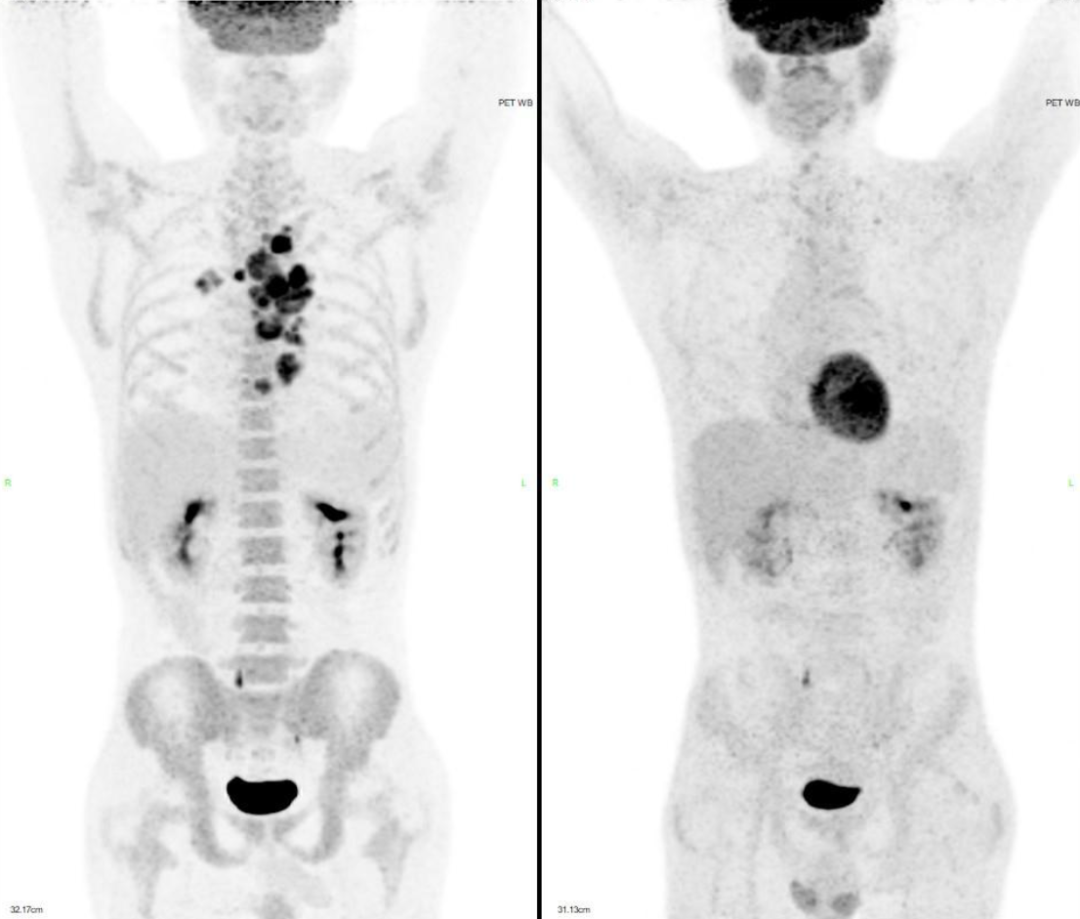

化疗后患者症状进一步缓解,于是我们按期再次给予上述方案化疗 1 疗程。2 疗程化疗后的 CT 评估,证实我们对患者化疗敏感性的推断,病灶有了明显的缩小,如下图 4:

我们第 3 疗程继续采用 GDP 为核心的靶向化疗,并计划采集干细胞,动员采集过程顺利,获得造血干细胞:5.02×106/kg 。遗憾的是完成了干细胞采集后患者进行了 CT 评估,患者肿瘤似乎没有进一步消退,进一步 PET-CT 评价,虽然和治疗前相比能达到 PR,但仍有较多活性残留,如下图 5:

2020 年的 9 月 16 日,患者进入移植舱开始完成预处理化疗,过程顺利,随后回输自体造血干细胞,CD34+ 5.56*106/kg,干细胞回输后第二天输注自体人源 CD20 CAR-T 2.06*106/kg。随着 CAR-T 细胞的输注,患者出现了明显的细胞因子释放反应,持续发热伴有血氧一过性降低,低流量吸氧及标准 CRS 处理后,得到控制。最终 CRS 评级为 2 级,没有出现神经系统毒性。过程中监测 CAR-T 扩增情况,在 CAR-T 回输后的第 13 天,达到了扩增高峰,见图 8。移植后第 14 天,中性粒细胞及血小板植入,入移植舱后 27 天,患者顺利出仓。出仓后 CT 显示,后纵隔肿块明显缩小,但出现左侧胸腔积液,如下图 6:

在患者完成自体移植联合 CAR-T 治疗后的 2 个月,终于迎来了首次 PET-CT 评估,结果达到了部分缓解,如下图 9:

考虑到患者既往 CAR-T 治疗后进展的病史,在移植后我们给予患者来那度胺进行维持治疗,并定期随访。令人惊喜的是,在随后观察的 1 年半中,患者肿瘤进一步缓解,最终达到完全缓解状态,患者下肢行走功能也完全恢复。随访 PET-CT 如下图 9: